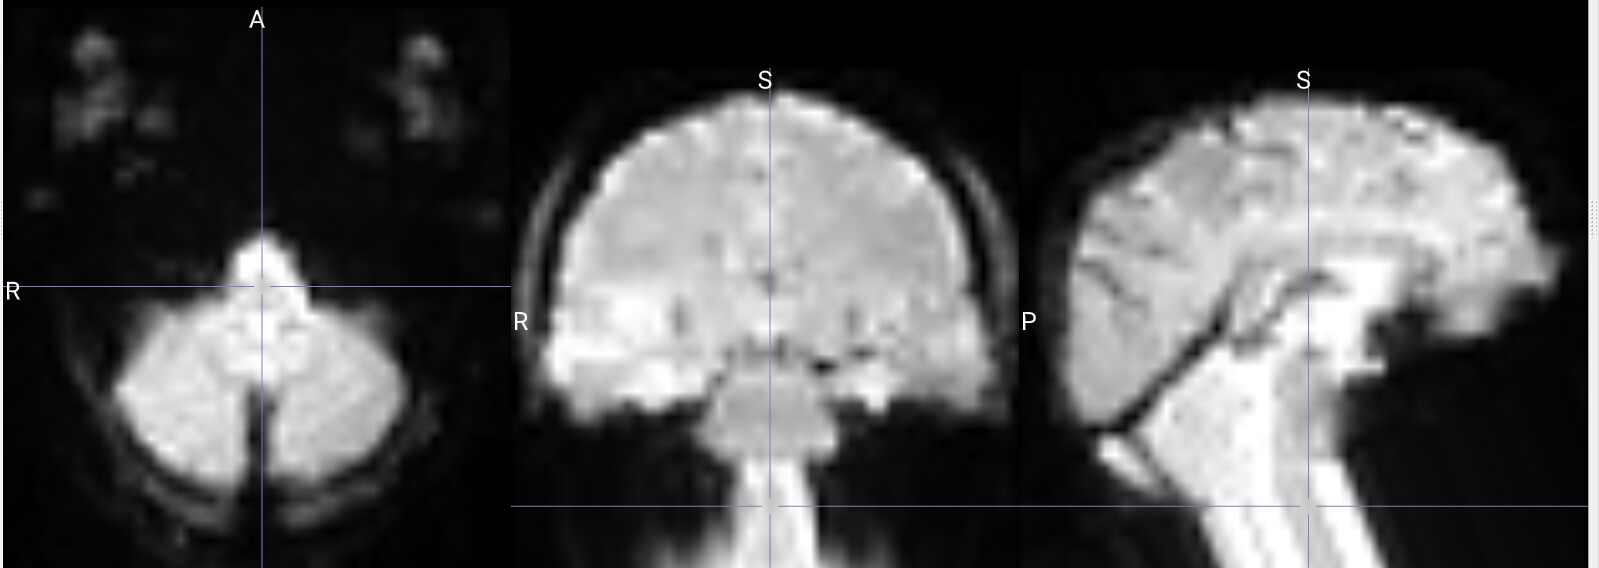

I am running fmriprep for the first time, and my preproc_bold.nii files have a weird distortion extending from the cerebellum for a few slices, it is basically a copy of what seems like the final slice, extending anteriorly.

The copied slices are overlapping with the superior slices, likely messing with the voxels.

images showing how it extends anteriorly: